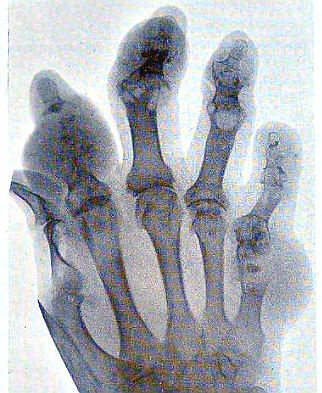

통풍을 옛날에는 ‘귀족병’이라고 했습니다. 기름진 음식과 술을 많이 마실 수 있는 상류층 사람들이 주로 걸렸기 때문입니다. 하지만 지금은 누구나 걸리고 점점 나이도 어린데서도 발생한다고 합니다.

바람은 푸린이라고 하는 단백질의 대사 이상으로 많아진 요산이 체내에 축적되어 관절과 조직에 침착하게 일어나는 병입니다. 따라서 체내에 요산이 과도하게 축적되지 않도록 푸딩이 많이 함유된 음식을 줄이고, 체내의 요산이 잘 배출되도록 해야 합니다.